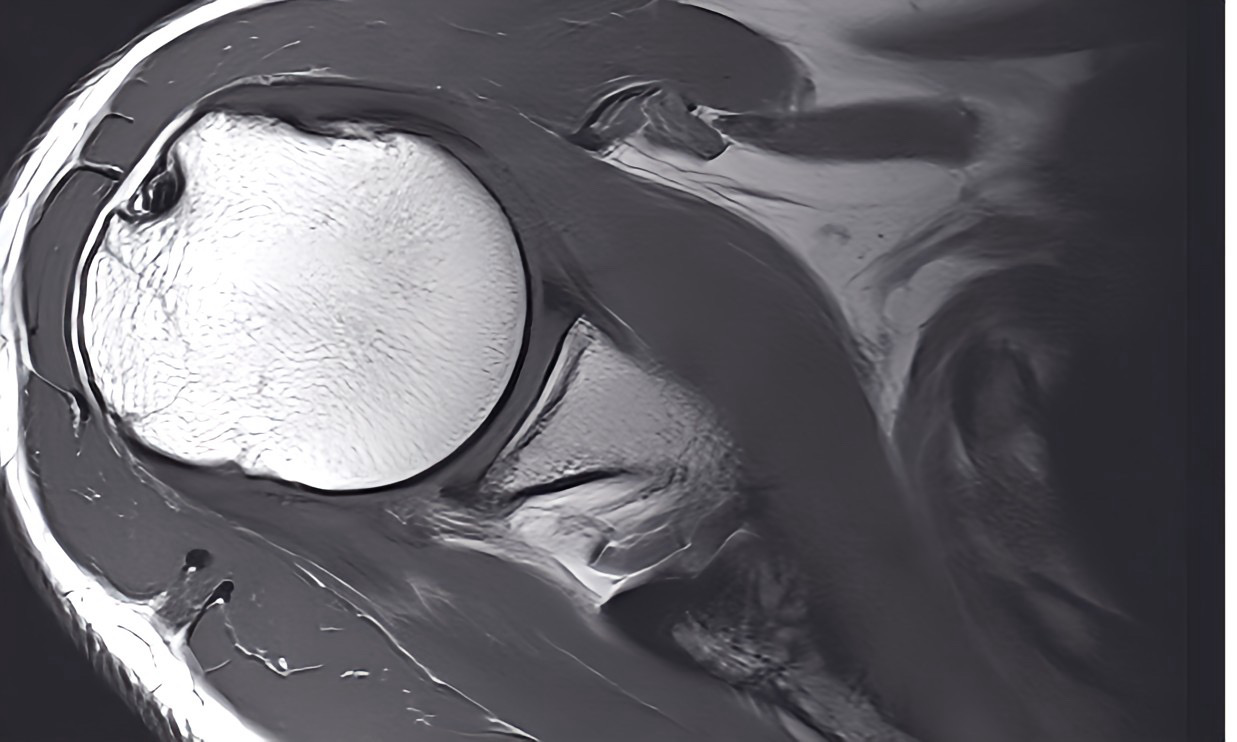

MRT-Auswertung

Egal, ob es sich um eine Erstdiagnose oder eine Zweitmeinung handelt – Dr. Kenawy biete Ihnen eine umfassende und professionelle MRT-Auswertung.